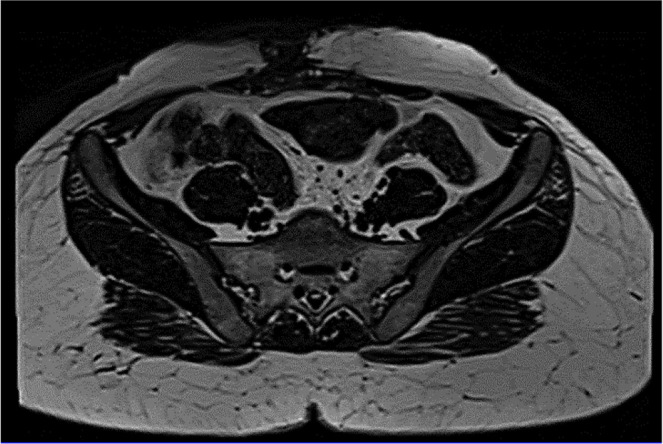

Case report: We report a case of a 26-year-old female presenting with painful swelling at a caesarean section scar, previously excised for similar complaints. Physical examination revealed a solid soft tissue mass on the scar. Magnetic resonance imaging (MRI) identified a 2x2 cm lesion in the right abdominal wall, suggestive of suture granuloma. Surgical excision revealed prolene suture material within the granulomatous tissue. Histopathology confirmed foreign body reaction.